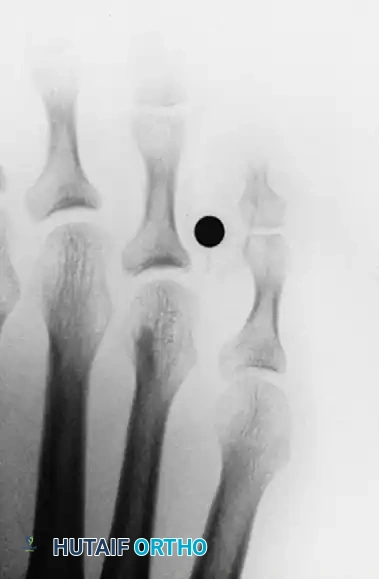

The lesion results directly from the focal pressure imposed by the lateral side of the base of the fourth proximal phalanx abutting against the medial condyle of the head of the fifth proximal phalanx (or a combination of both).

- Osseous Resection: Expose the prominent medial condyle of the fifth proximal phalanx head. Using a micro-sagittal saw or a sharp rongeur, perform a partial condylectomy. Resect enough bone to ensure that no impingement occurs when the toes are manually compressed together. If the lateral base of the fourth proximal phalanx is also prominent, a conservative resection of this flare is performed.